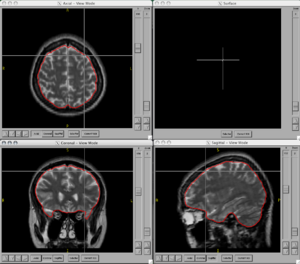

BRAINSCut is a software package for segmentation of structures using artificial neural networks. Currently this tool supports the segmentation of the following structures: brain, caudate, putamen, thalamus, hippocampus, anterior cerebellum, interior posterior cerebellum, superior posterior cerebellum, corpus medullary. Future regions will include the globus pallidus, amygdala, and nucleus accumbens. The command line uses the Slicer3 execution model framework.

Figures

- BRAINSCut